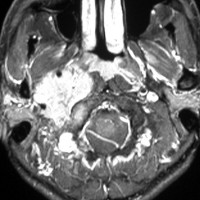

耳の聞こえと飲み込みが悪くなって発症(難聴と嚥下障害)した20代の患者さんのグロームス腫瘍 jugular paragangliomaです。左の頚動脈撮影 CAGでは,頸部の腫瘍におされて内頚動脈が前方に屈曲しています。外頚動脈から多くの血管が流入して血管腫のように濃い腫瘍陰影がみえます。右側の椎骨動脈撮影 VAGでは,頚静脈孔から頭蓋内の小脳延髄角部まで伸びた腫瘍が染まります。頭蓋内はPICAから頸静脈球と頸部には椎骨動脈の筋肉枝からの腫瘍血管がみられます。

頸部から頸静脈球を抜けてS上静脈洞内に入ります。これはクラスCかDか迷うところです。ちょっと難しい。またこのサイズでは,迷走神経と舌咽神経の機能を温存することができません。延髄方向へ伸展していますし年齢が若いので手術せざるを得ないものでした。

この腫瘍は放射線治療で制御できるものではないでしょう。手術で全摘出できて10年以上再発はありません。嚥下障害と強い嗄声が残りましたが,働いて社会生活はできています。